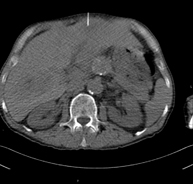

- Abdomen CT

Diagnostic test that involves obtaining high-definition anatomical images of the abdomen (liver, gallbladder, bile duct, pancreas, spleen, stomach, intestines, kidneys, vascular structures, bladder, uterus and ovaries, etc.) using CT (computed tomography) equipment. These images are then studied at a workstation capable of producing two-dimensional reconstructions in different spatial planes, and also 3D (volumetric) reconstructions. Most studies require the use of iodinated contrast to improve image definition.